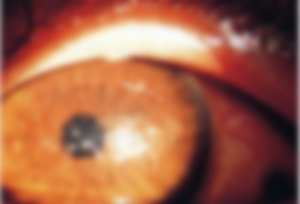

目の視界の中心に吸い込まれるようにして動く灰色?白い? モヤモヤが現れます。 両目で見え、視界を動かしても常に中心に見えます。 また目などを30秒ほど押さえても、変わりはなく家など太陽光のあたらない場所へ 視界のキラキラ、原因は? キラキラとしたものが視界に映った時に一番に考えられるのは「 閃輝暗点 」という病気です。 それでない場合には、「 飛蚊症 」「 光視症 」といった病気が原因として有力です。 それぞれについて、原因や治療法についてみてみましょう。No043-黒いものが視界に見える 黒い点や虫のようなもの、または薄い雲のようなものが視界にみえるということで受診される方が一日に3,4人はおられます。 この症状を飛蚊症(ひぶんしょう)といいます。 症状であって病気の名前ではありません。 目

視界に現れる異常 飛蚊症と光視症

目にもやもやしたものが見えた時に潜む怖い病気 医療法人クラルス はんがい眼科 目のブログ